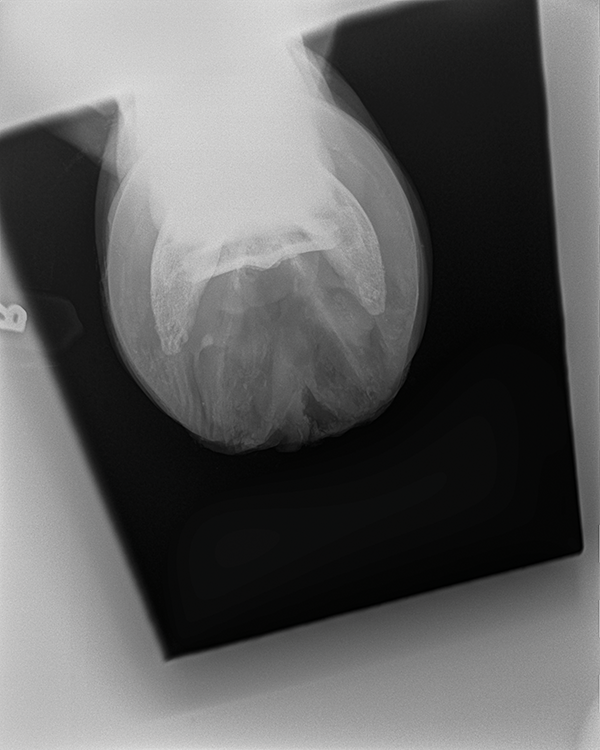

lateral coffin bone projection

45 degree dorsopalmar coffin bone projection

lateral navicular projection

skyline (palmar proximal) navicular projection